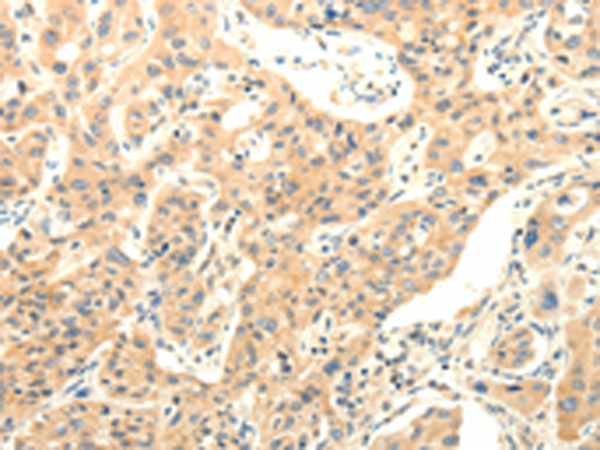

分类: 科研抗体货号: P11175别名:应用: IHC反应种属: Human